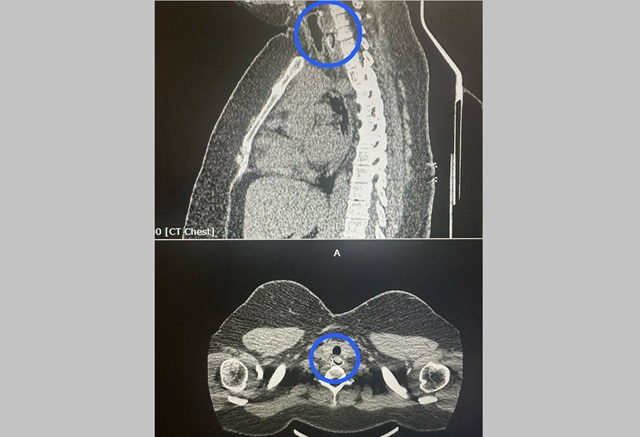

КТ показало, что косточка практически закрыла просвет пищевода. Достать инородное тело через рот было невозможно. Торакальные хирурги разрезали шею, пищевод и аккуратно извлекли косточку.